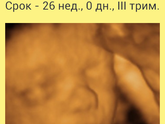

Вот и 30 неделек, не успею оглянуться, как скоро обниму свое маленькое счастье, и привезу домой сладкую сестричку своей Евчуле?

На плановую госпитализацию мне в,37 недель, для снятия пессария, врач сказала, что возможно меня не отпустит, и родим в близжайшее … Читать далее